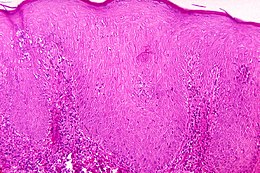

Description de l'image Pinta (disease).jpg.

La Pinta ou « caraté » est une tréponématose, une maladie tropicale chronique de la peau causée par le spirochète Treponema carateum. Elle atteint les enfants et adolescents des régions tropicales et forestières d'Amérique Centrale et d'Amérique du Sud.

C'est une affection relativement bénigne, entraînant uniquement des lésions cutanées, d'abord inflammatoires puis dyschromiques. Le diagnostic est clinique et sérologique. Le traitement repose sur les antibiotiques tels que la pénicilline, la tétracycline ou le chloramphénicol.